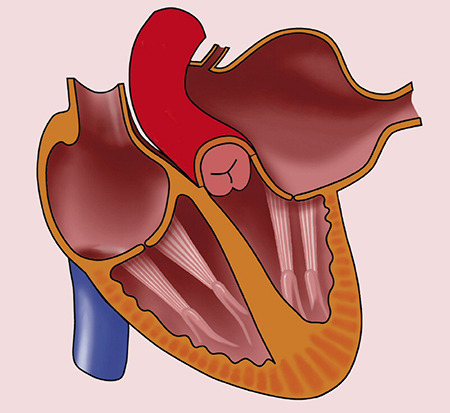

گاهی ممکن است مشکلی در بطن چپ شما وجود داشته باشد که خون را به آئورت پمپ میکند. برخی افراد هم مشکلی در دریچه میترال دارند که اجازه میدهد خون بین دهلیز چپ و بطن چپ حرکت کند. این مسائل میتوانند فشار بالا و/یا حجم زیاد خون در دهلیز چپ ایجاد کنند.

• بیماری دریچه میترال

• بیماری دریچه آئورت

• تنگی دریچه آئورت (دریچه آئورت باریک)

• تنگی دریچه میترال

• نارسایی دریچه میترال

• انجام پروسیجرها یا جراحی برای رفع مشکلات دریچه

• مصرف دارو برای تسکین علائم مشکلات دریچه

فقط در صورت وجود مشکل دریچهای شدید (مثل تنگی یا نارسایی میترال) ممکن است جراحی لازم باشد.